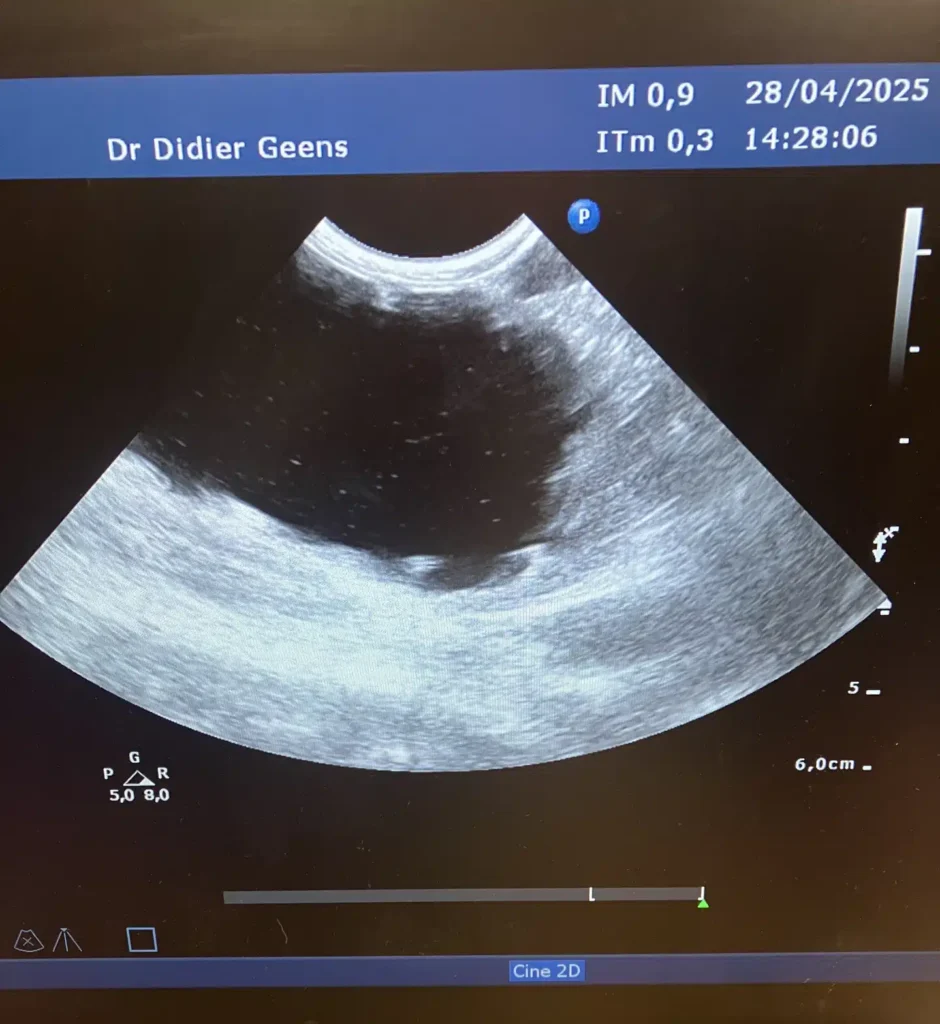

Petit chien qui a une insuffisance rénale diagnostiquée à la prise e sang; L'échographie montre que les reins sont remplacés en grande partie par une cavité remplie de liquide, ce qui a permis de conclure que malheureusement il n'y avait pas de traitement possible.